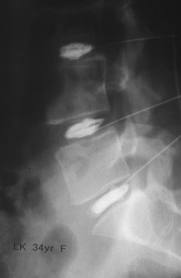

Figure 5: Note the far lateral disc bulging into the osseoligamentous canal at the L5-S1 disc level. Also appreciate the degenerative loss of disc space height at the L5-S1 level ... Fetch This Document